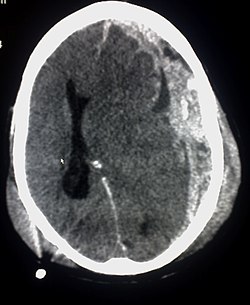

Intrakranielle, intrazerebrale Blutungen

Die intrazerebrale Blutung liegt im Gehirn und resultiert in einer Beeinträchtigung der Hirnfunktion, für die das betroffene Hirngewebe benötigt wird. Durch Größe und Lokalisation der Blutung wird deren raumforderndes Verhalten bestimmt. Gefürchtet ist die mit einer Mortalität von 50 bis 60 % im ersten Jahr nach der Blutung einhergehende Hirnmassenblutung, die große Teile des Gehirns zerstört und zu einer Einklemmung führen kann.

Bild: Subdurale Blutungen bilden im Computertomogramm hingegen meist eine konvex-konkave Form, hier linksseitig (Ansicht von unten, im Bild also rechts)